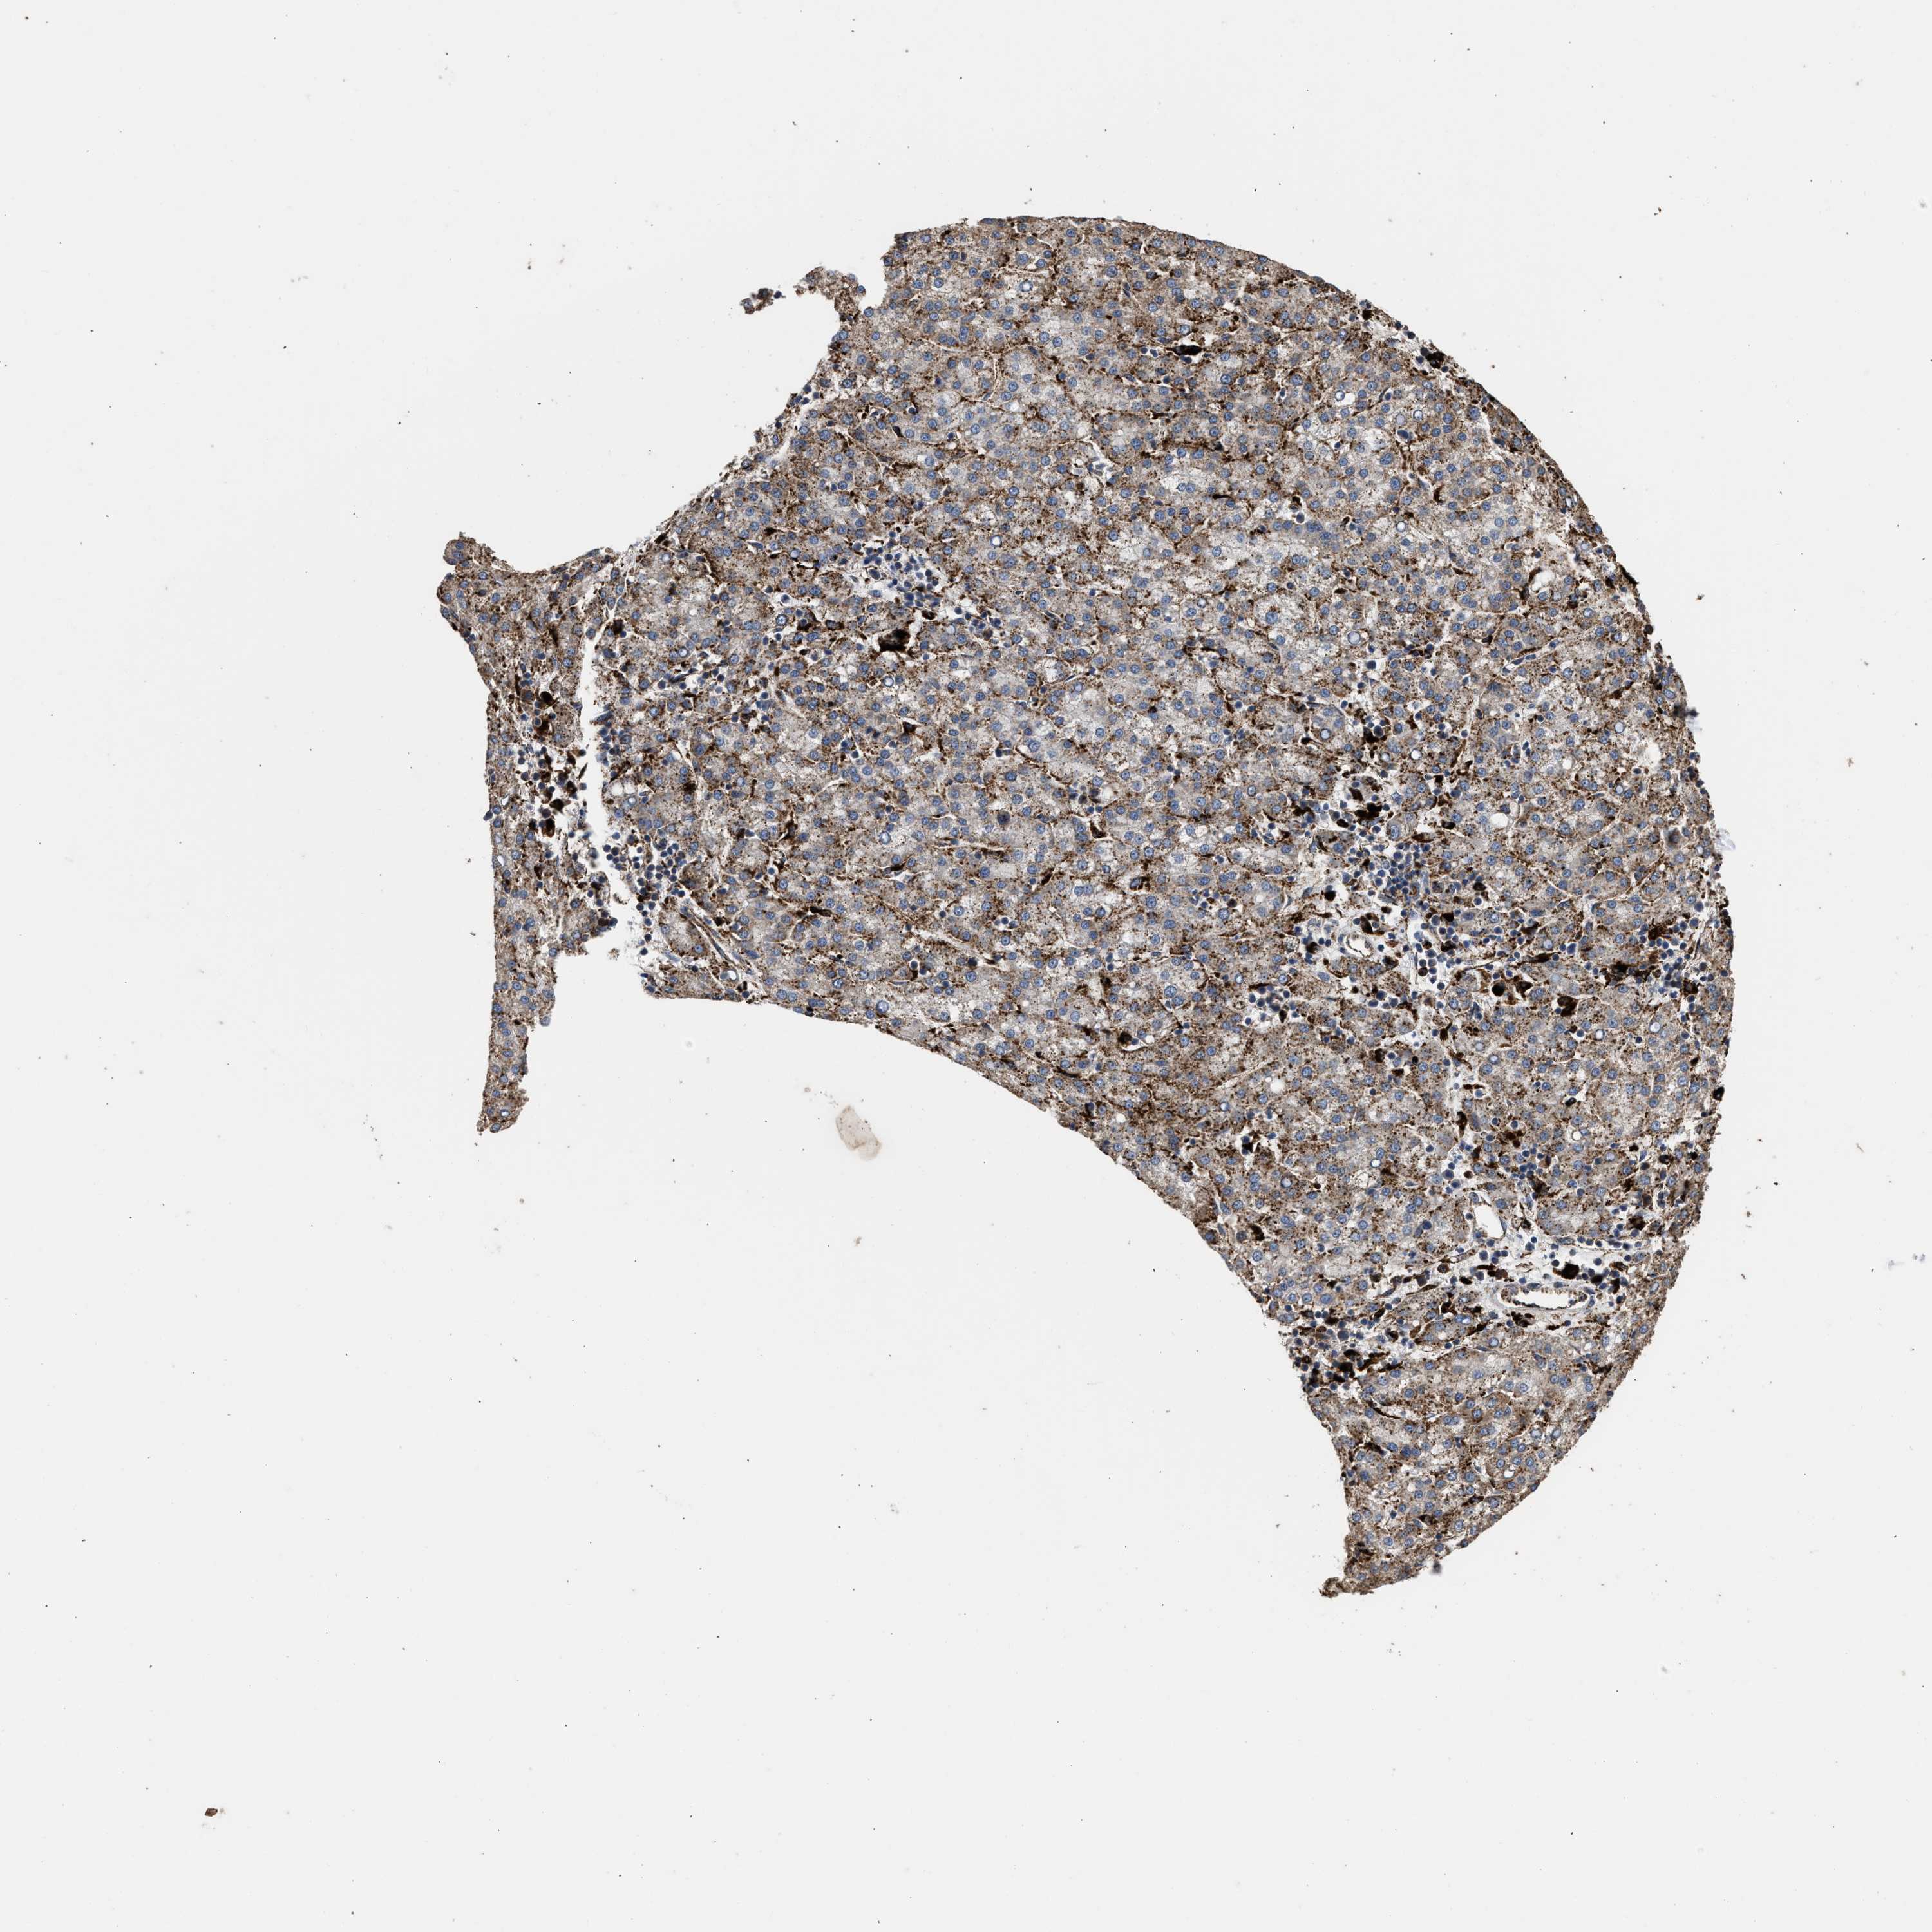

LIVER CANCER - Protein expressioni

A mouse-over function shows sample information and annotation data. Click on an image to view it in a full screen mode. Samples can be filtered based on level of antibody staining by selecting one or several of the following categories: high, medium, low and not detected. The assay and annotation is described here.

Note that samples used for immunohistochemistry by the Human Protein Atlas do not correspond to samples in the TCGA dataset.

Antibody stainingi

Antibody staining in the annotated cell types in the current human tissue is reported as not detected, low, medium, or high, based on conventional immunohistochemistry profiling in selected tissues. This score is based on the combination of the staining intensity and fraction of stained cells.

Each image is clickable and will lead to virtual microscopy that enables deeper exploration of all samples and also displays staining intensity scores, fraction scores and subcellular localization as well as patient and tissue information for each sample.

Antibody CAB017112

Staining

High

Medium

Low

Not detected

Intensity

Strong

Moderate

Weak

Negative

Quantity

>75%

75%-25%

<25%

None

Location

Nuclear

Cytoplasmic/membranous

Cytoplasmic/membranous,nuclear

Cholangiocarcinoma

Carcinoma, Hepatocellular, NOS